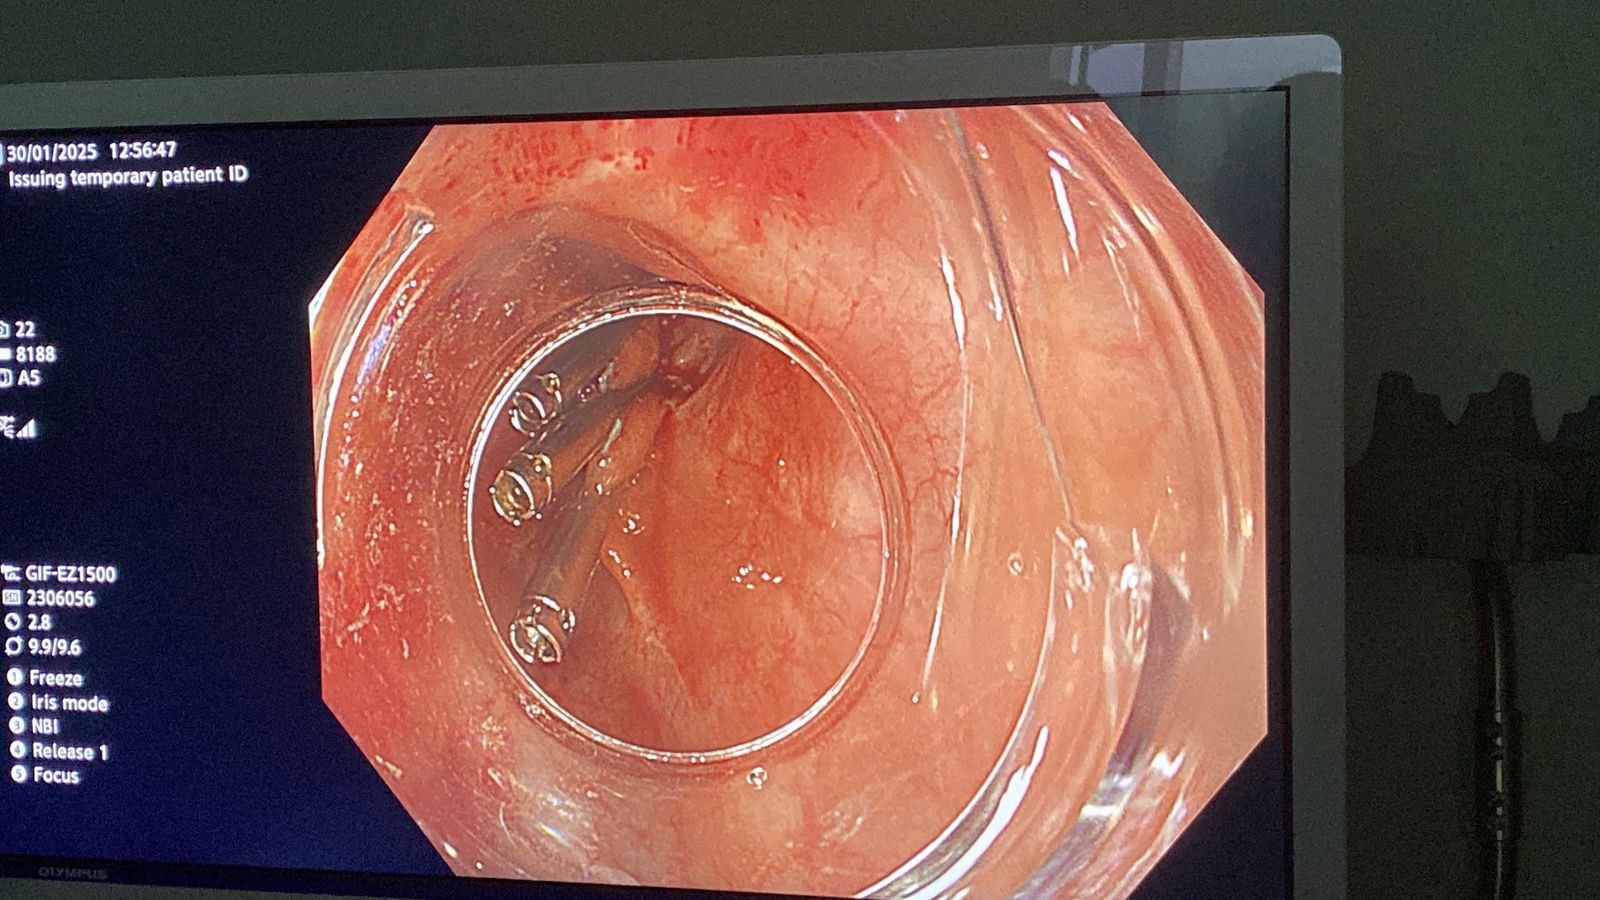

إنجاز طبي جيد.. نجاح أول عملية منظار موجات فوق صوتية لتشخيص واستئصال ورم بالمريء في جلسة واحدة دون جراحة بوحدة المناظير بكلية الطب جامعة حلوان وذلك لأول مرة بمستشفى بدر الجامعي، في إضافة جديدة لسجل إنجازات الوحدة الطبية .

-تمت العملية في غضون 30 دقيقة باستخدام تقنية مناظير الفراغ الثالث، حيث تم تحديد نوع الورم ومكانه وحجمه ومنبعه عبر منظار الموجات فوق الصوتية، ثم استئصاله مباشرة في نفس الجلسة.

-وأجريت العملية تحت إشراف الدكتور شريف البحيري، مدرس الباطنة العامة بكلية الطب واستشاري المناظير التداخلية ومناظير الفراغ الثالث، والذي تلقى تدريبا متخصصا على هذه التقنية المتقدمة في جامعة كاتب أتاتورك بتركيا خلال مهمة علمية من جامعة حلوان.

-يحتاج إجراء مثل هذه العمليات في نفس الوقت لتوفر أجهزة متقدمة مثل جهاز الموجات فوق صوتية و مناظير متقدمة لإجراء استئصال الورم، و أدوات وآلات جراحية دقيقة في نفس توقيت اجراء العملية ، كما أنه يلزم توافر خبرات و مهارات للفريق المؤدي للعملية و ذلك لأخذ قرار الاستئصال، الذي يعتمد بشدة على مدى دقة التشخيص و أيضا على تحديد سريعا لخطة لاستئصال الورم و إجراء الاستئصال بدقة حتى لا يتعرض المريض لأي مضاعفات اثناء العملية.